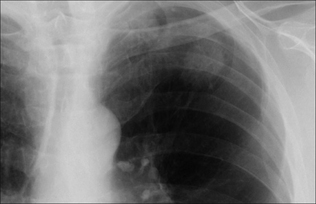

image

Figure 20.5 The right upper zone nodule has a cavity within it. Some benign lesions do cavitate, e.g. abscess or rheumatoid nodule. All the same, in the appropriate clinical setting, cavitation should always suggest the probability of a squamous carcinoma. Subsequently confirmed squamous carcinoma of the bronchus.